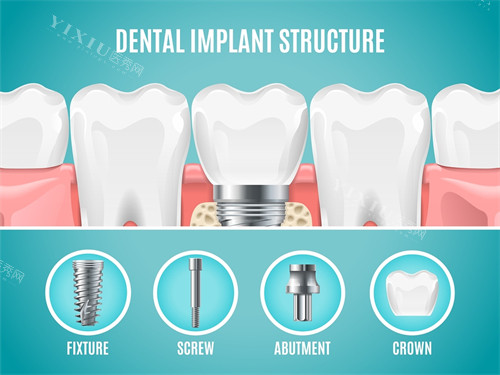

牙槽骨的质量和数量是首要考虑因素。上门牙区域的牙槽骨需要具备足够的高度和宽度来容纳种植体,通常要求剩余骨高度不低于10毫米,宽度不少于5毫米。由于上门牙区域靠近鼻窦,骨量不足的情况较为常见,这需要通过特色影像检查比较准评估。骨质密度同样重要,理想的骨密度能够为种植体提供良好的初期稳定性。骨质疏松或长期缺牙导致的骨吸收患者可能需要先要进行骨增量手术。

三维位置正确性对美学结果至关重要。种植体植入的深度、角度和位置需要精细规划,既要确保良好的生物力学分布,又要为修复体提供理想穿龈轮廓。现代导板技术有助于实现精密植入,但医生经验仍是成功的关键因素。

详细的影像学检查不可或缺。锥形束CT能够明确评估剩余骨量、骨密度及重要解剖结构的位置关系。对于复杂病例,智能化模拟技术可以帮助规划种植体三维位置。常规口腔检查需要评估邻牙和咬合状况,存在问题的牙齿需要先要进行治疗。